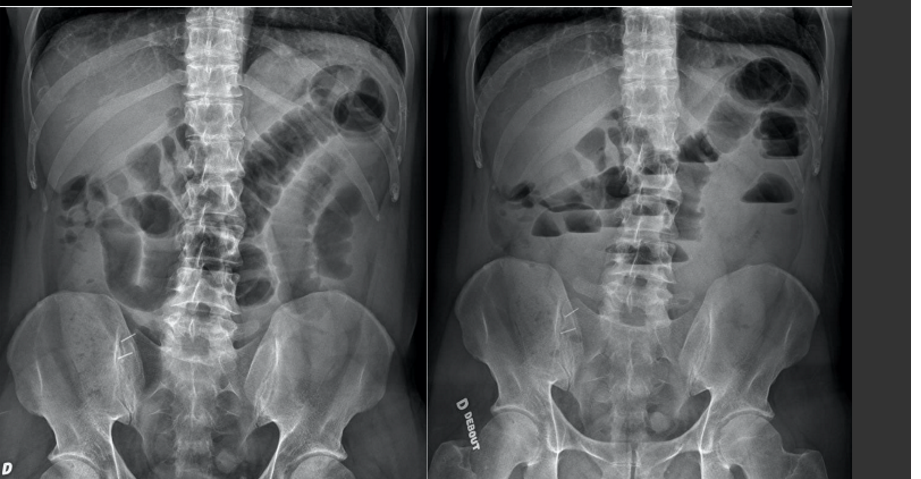

patho?

A

Illéus paralytique

1–) importance de la dilatation

très très dilaté –) paralytique fera pas ca

2–)ne voit pas ou très peu de niveux hydro-aérique( MEILLEUR TRUC SI T’ÉTAIS CAPABLE EN VOIR)

3–)Si capable voir air dans le rectum en bonne qté –) surement pas obstruction mécanique